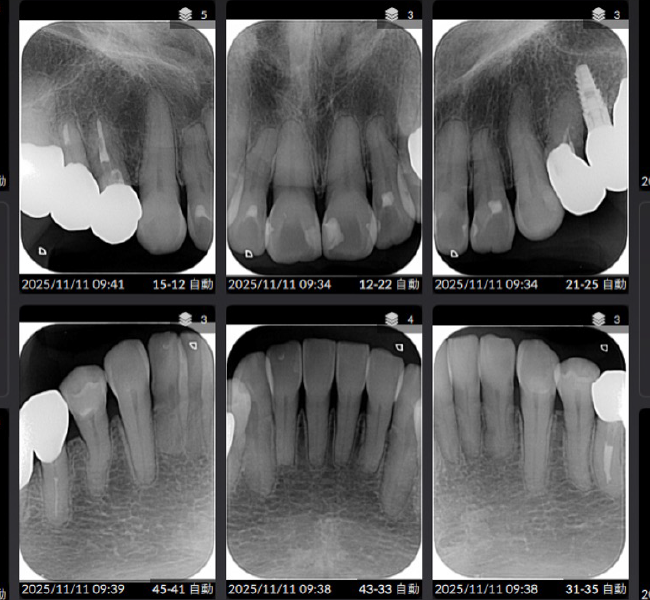

治療後